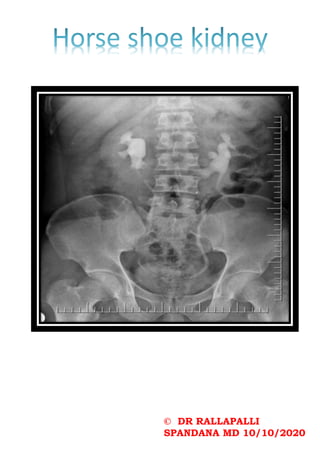

Hyperinflated lungs: increasedradiolucency of lungs Flattening of domes of diaphragm Pulmonary infiltrates Segmental collapse